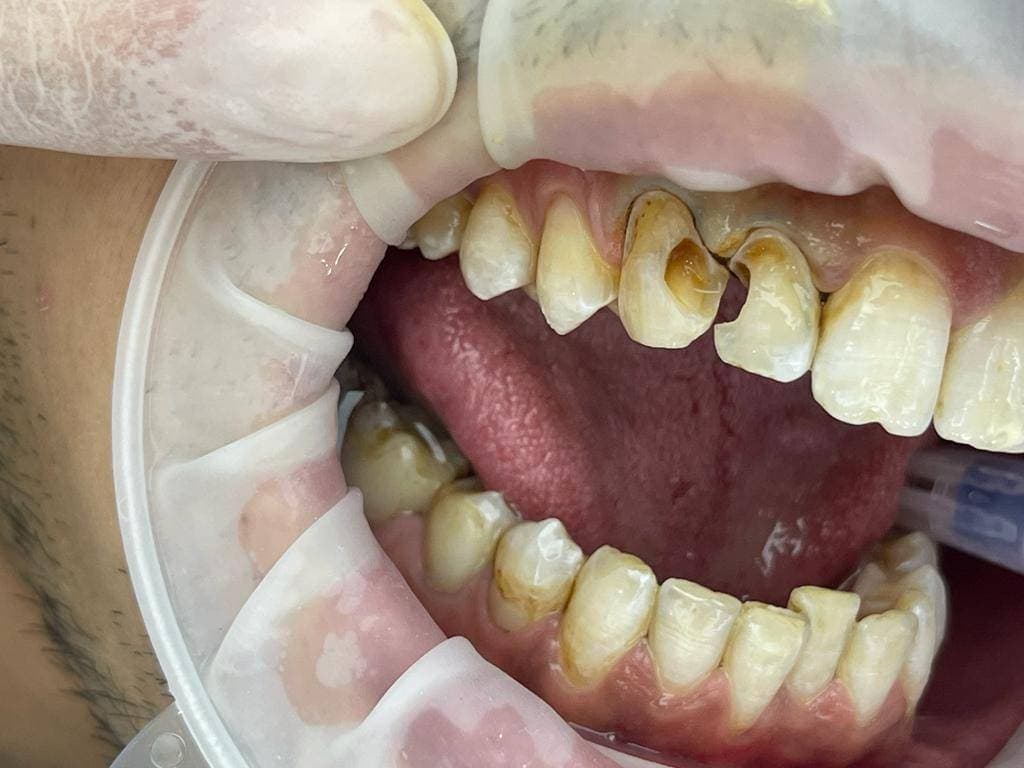

Caria secundară marginală apare pe coroana unui dinte obturat, la nivelul limitei de contact dintre marginea cavităţii şi materialul de obturaţie, de obicei din cauza unei igiene precare . Aceasta are tendinţa de a evolua către pulpa dentară, provocând infectarea acesteia sau chiar fracturarea peretilor dentari.

Caria secundară marginală este o afecțiune dentară care apare atunci când caria se dezvoltă la nivelul marginii sau a suprafețelor de contact ale unei plombe sau proteze dentare. Această afecțiune poate fi cauzată de mai mulți factori, cum ar fi:

Simptomele cariei secundare marginale pot include sensibilitate la cald sau rece, durere la masticație, inflamația gingiilor și apariția cariilor la nivelul marginii plombei sau protezei dentare.

Tratamentul cariei secundare marginale implică îndepărtarea cariei și a plombei sau protezei dentare deteriorate, urmată de aplicarea unei noi plombe sau proteze dentare. Este important să urmați o igienă orală adecvată și să vizitați regulat dentistul pentru a preveni apariția cariilor și a altor probleme dentare.